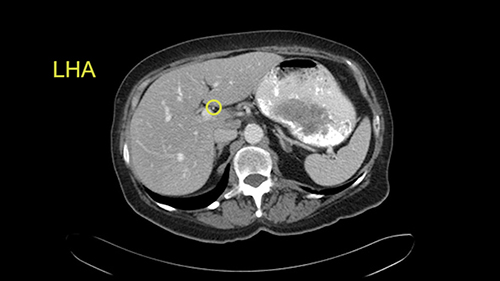

The procedure-specific slowing down moments from a technical point of view for a right hemihepatectomy include a careful evaluation of the inflow structures including the right hepatic artery, the right portal vein, as well to make sure that I have identified and preserved the left hepatic artery and the left portal vein at all times, and minimize any injury or dissection of the common bile duct. Also, I am careful when I mobilize the right liver, not to tear the right triangular ligament and cause bleeding of the liver as I mobilize it off the retroperitoneum and the bare area. In addition, the last procedure-specific slowing down moment is to carefully identify the right hepatic vein and ensure that I encircle it safely without damaging the IVC or the middle and left hepatic vein structures at all times.

In addition, as I plan this operation, I will also look at the size of the small tumors. They’re very small, some are less than one centimetre in size, and carefully evaluate the relationship between the small tumors and the surrounding vascular structures. If I cannot see or feel the tumors at the time of surgery, I will use the blood vessels in order to landmark and plan my operation.

![[RHA]](jpg/preop_sg_moment3.jpg)